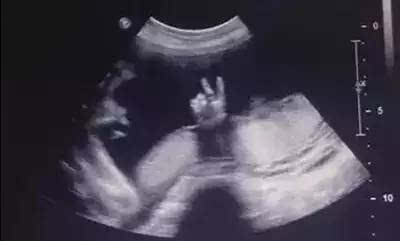

医生正在准备器械,晴晴在床位上突然感觉宝宝有了胎动,晴晴兴奋得喊道:“宝宝在肚子里动呢。”医生适时地调试好仪器,显示屏上顿时有了画面。

医生一边为宝宝做检查一边说:“胎动不一定是真的动,你那种胎动的感觉是不是一耸一耸的?你看宝宝在打嗝呢。”看着屏幕上可爱的小宝宝,晴晴好想快点和孩子见面。

除了活动手脚这一类大运动可以被孕妈察觉,其余一些面部表情和手部精细动作宝宝都在“偷偷”进行。至于这些动作之间的区别,如果不是借助B超等医疗手段,单凭孕妈感知是无法分辨的。

在38周后胎儿体积已经接近足月婴儿标准,子宫内没有多余空间供宝宝活动,此时宝宝的全身动作减少,孕妈明显感到胎动减少,在B超下仅能观察到呼吸、打哈欠等细微面部表情。